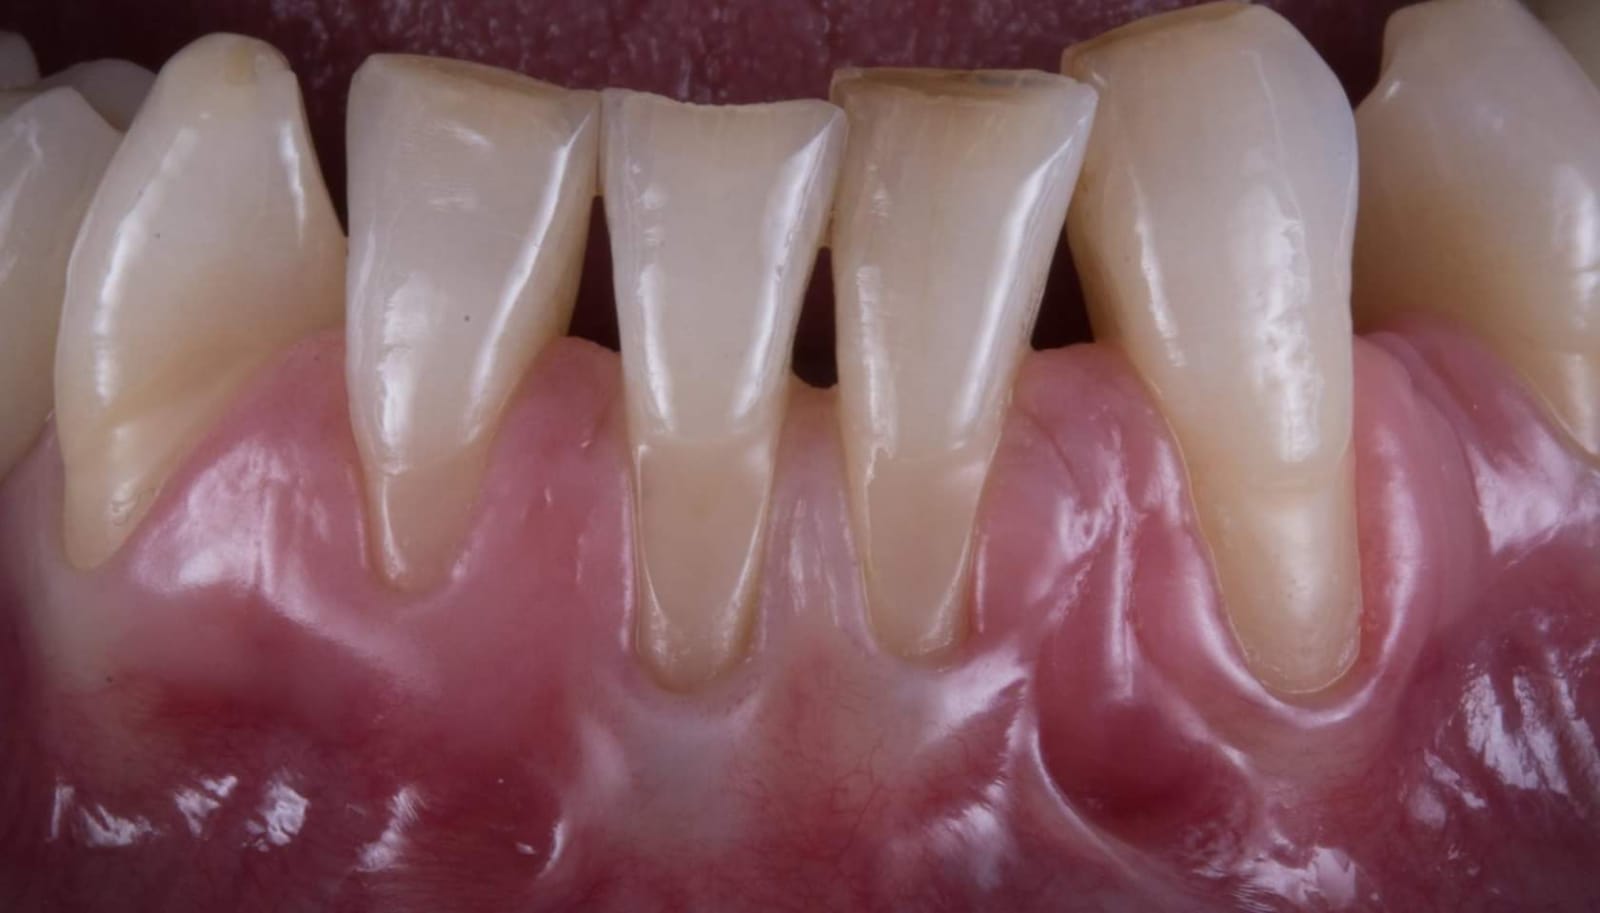

Questa la foto finale…

2